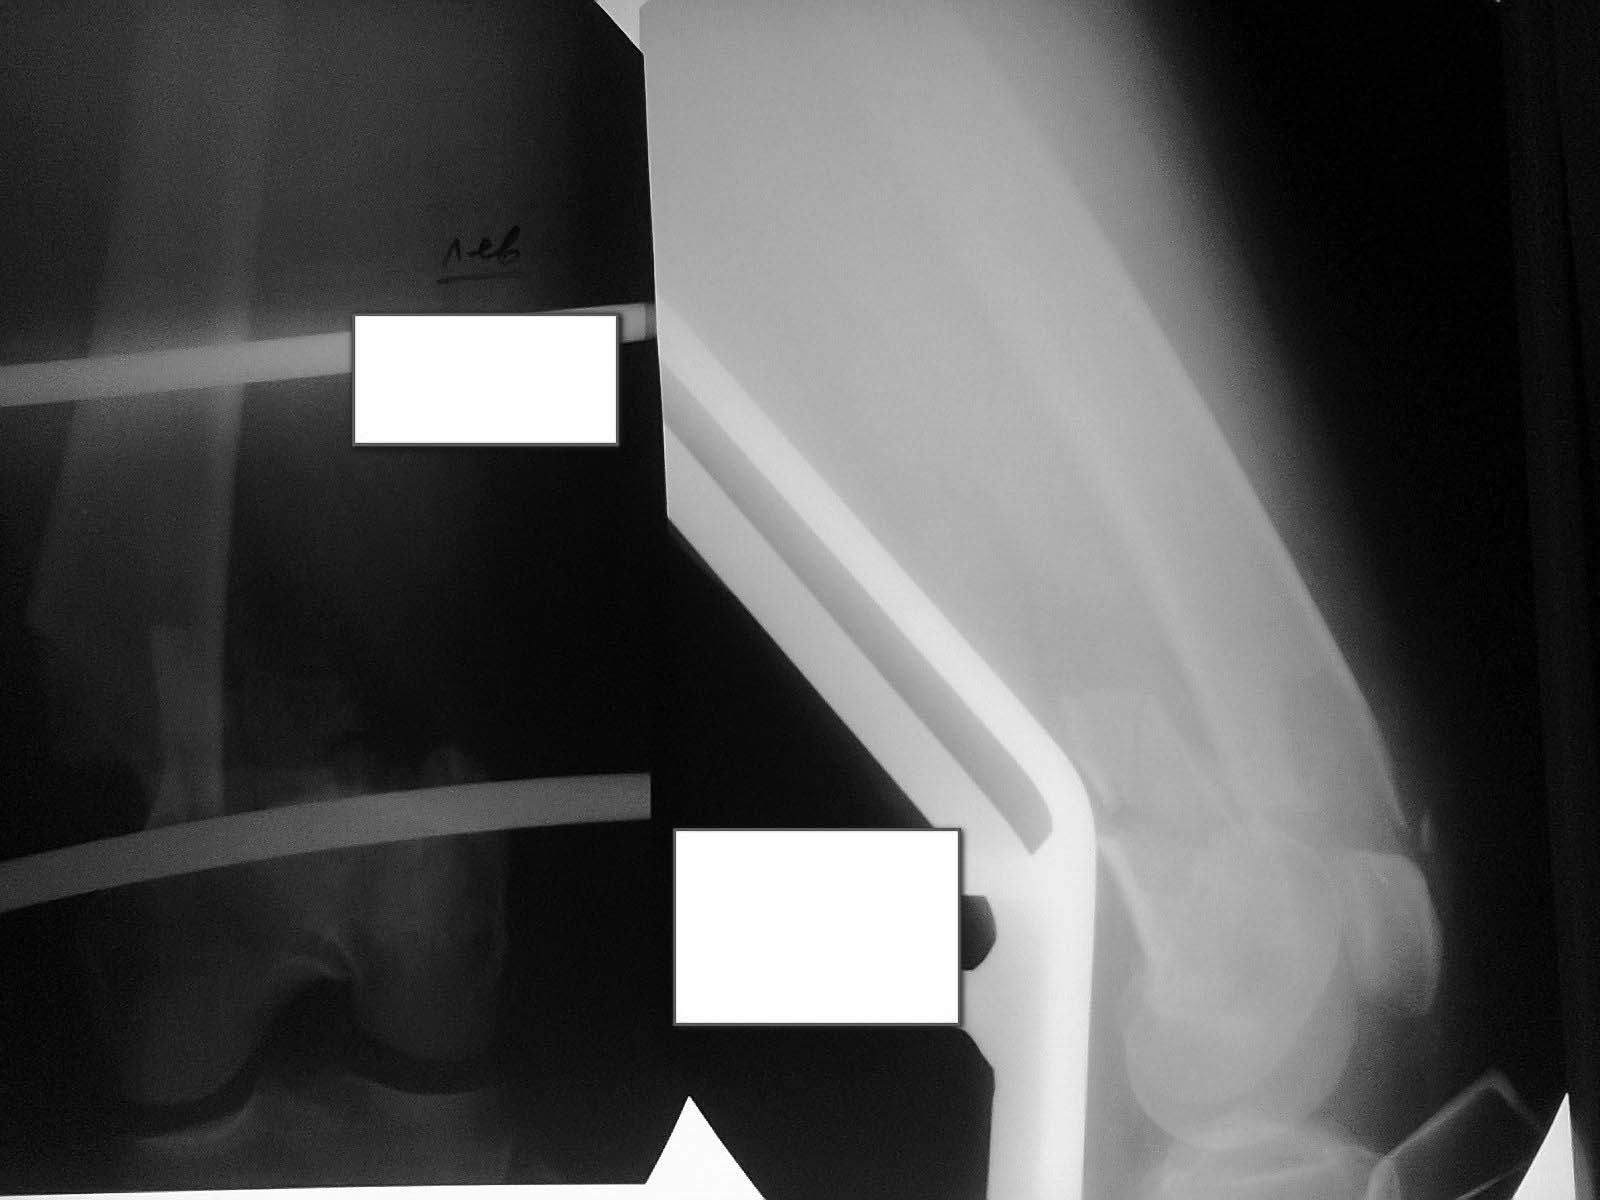

Представляю пациентку Д., 57 лет.Пострадала в ДТП в августе 2014 г.Диагноз:Открытый оскольчатый внутрисуставной перелом дистального метаэпифиза левой бедренной кости со смещением отломков. Рваные раны и ссадины левых бедра и голени. Закрытый перелом V ребра слева без смещения отломков. Травматический шок I ст(снимок 1).